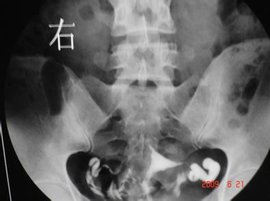

宫角妊娠_360百科

768x576 - 40KB - JPEG